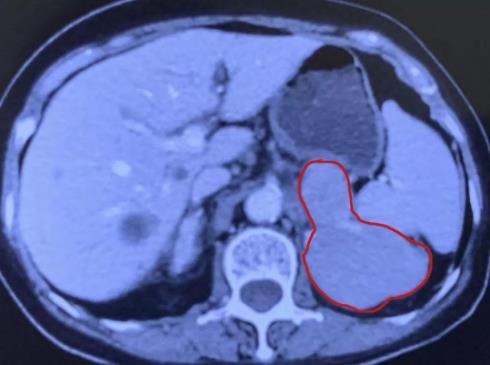

廣州復大腫瘤醫院的冷凍專家團隊立刻組織了會診,他們評價狀況:此次病情跟十年前、三年前都不一樣,以往的腫瘤比較小,大概三公分左右,可以做到控制性的消融,但是這次的腫瘤超過了十公分,原則上,只能做一個姑息性的消融。據廣州復大腫瘤醫院副院長牛立志教授介紹,“因為考慮到老人家身體虛弱,年齡大,腫瘤大,我們考慮做一個姑息性的消融,主要是為了減輕負荷,減少疼痛。術中我們一共插了六根針,大約將90%的腫瘤做了消融。”術后老奶奶身體正常,回到家鄉醫院調養身體。

兩個月后,李阿婆回到廣州復大腫瘤醫院進行復診。根據以往經驗,醫生們原本打算對她的病情進行第二次消融的,但經過影像學檢查,發現剩余的腫瘤基本已經完全壞死了!也就是講原本只消融了90%的腫瘤,現在連剩余的腫瘤也死亡了,老人家完全不需要做第二次消融了!這個意外的驚喜令李阿婆與家人感到特別地開心,李阿婆家人評價說:“真沒有想到廣州復大醫院竟然會有這樣的技術!”